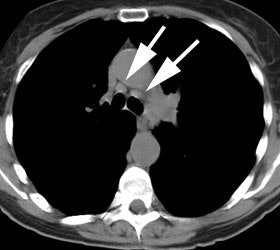

A central cancer near the aortopulmonary

window, as in this case, is difficult to separate from

possible mediastinal lymph nodes. |